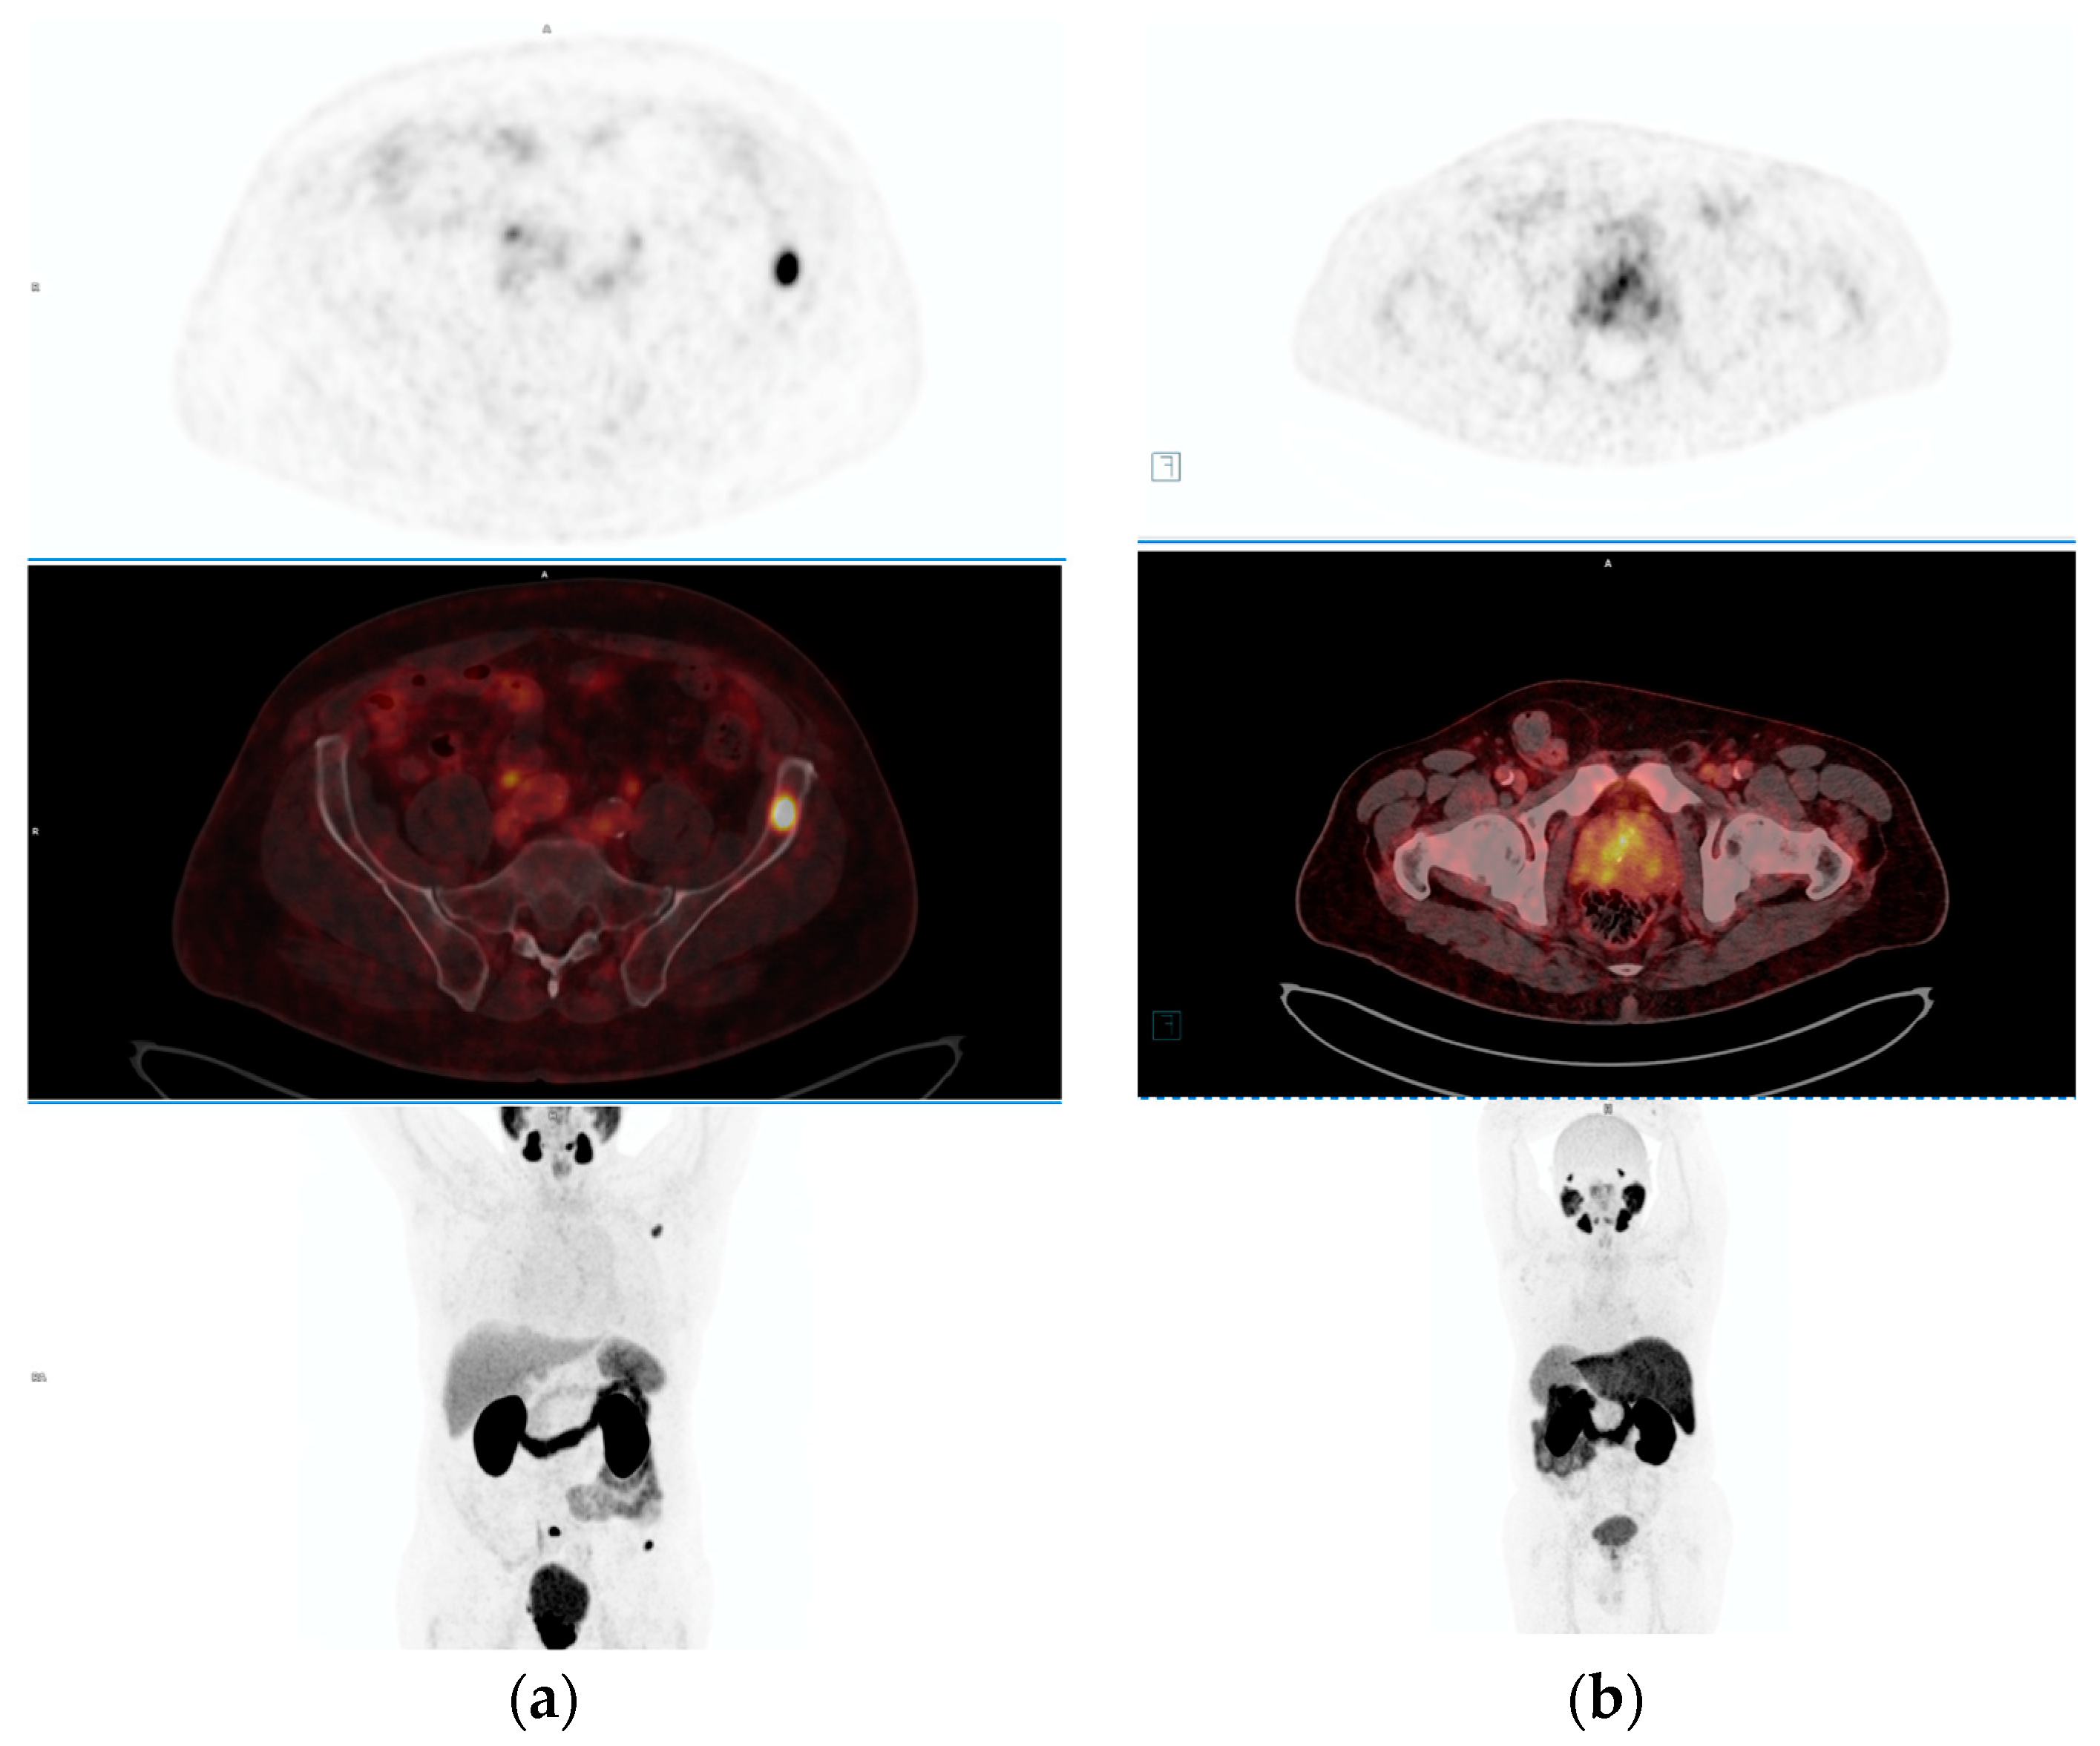

- Tayara, O.M.; Pełka, K.; Kunikowska, J.; Malewski, W.; Sklinda, K.; Kamecki, H.; Poletajew, S.; Kryst, P.; Nyk, Ł. Comparison of Multiparametric MRI, [68Ga]Ga-PSMA-11 PET-CT, and Clinical Nomograms for Primary T and N Staging of Intermediate-to-High-Risk Prostate Cancer. Cancers 2023, 15, 5838. [Google Scholar] [CrossRef]